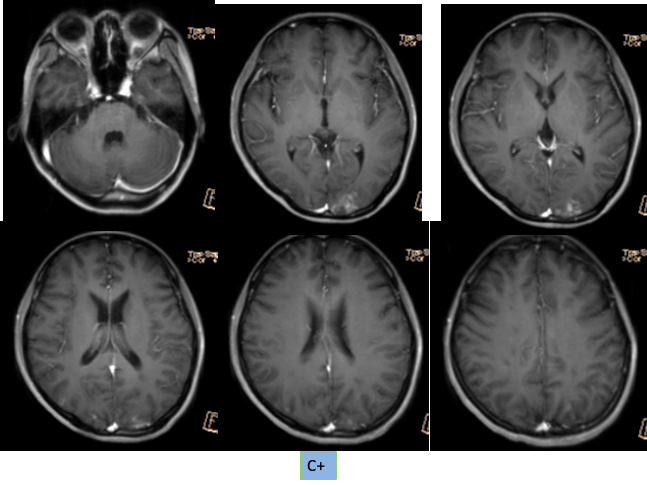

1. 本病例影像学表现提示的诊断线索:青年女性,脑内新见散在多发病灶,散在分布于多个脑动脉供血区,包括幕上幕下,皮层及深部白质,无明显占位效应,病灶周围无水肿,弥散受限,增强扫描左枕叶较大病灶不均匀强化,余病灶无明显强化。

定性诊断:本病例特点为青年女性,有明确肺癌病史,无明确神经系统症状,CT 发现颅内新发多发病灶,结合病史首先不除外转移瘤,MR 进一步检查病灶符合多发急性期脑梗死,确诊脑梗死不难,难的是确认脑梗死的发病原因。

MRI:长 T1、长 T2 信号,瘤周水肿广泛,占位效应明显,增强后实性肿瘤明显强化,坏死囊变可呈环形、不规则结节状强化。